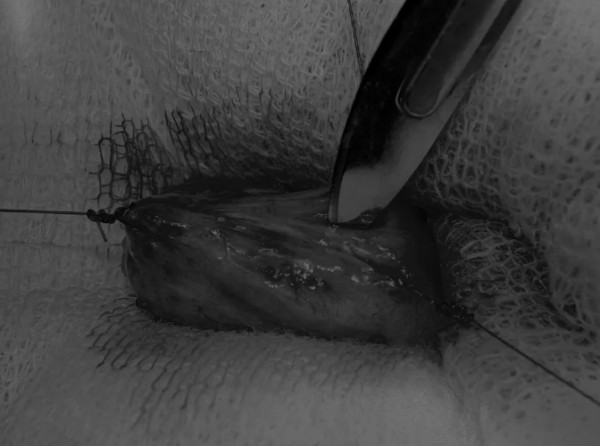

在中线开腹手术后,确定膀胱,将其取出并隔离(图1)。为了使膀胱持续暴露,可在膀胱中线两侧各放置一根固定缝线(图2)。

图2 在手术过程中,还需要另外两根固定缝线来保持膀胱切开术的膀胱边缘处于暴露状态